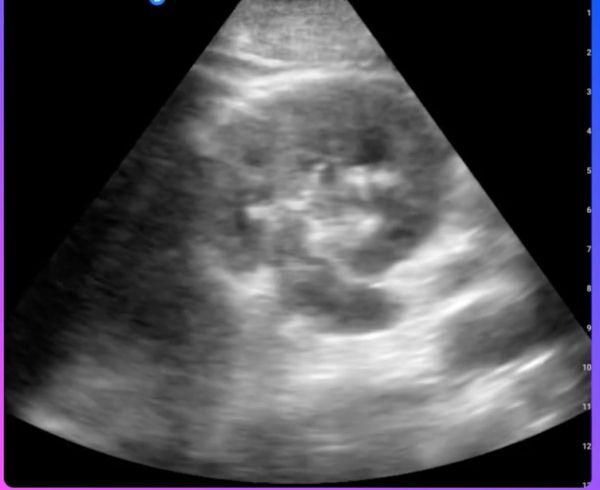

Can a New AI-Powered Point-Of-Care Ultrasound Platform Enhance Reporting Efficiency and Compliance?